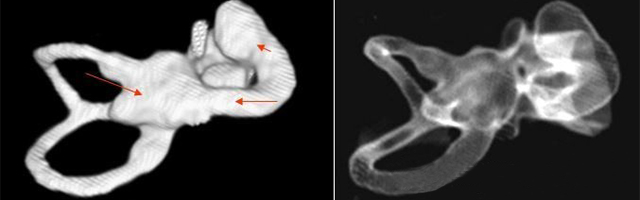

主要依靠顳骨高分辨CT和內(nèi)耳MRI。

雙側(cè)內(nèi)耳畸形:左側(cè)無內(nèi)耳迷路及內(nèi)耳道機構(gòu),為米歇爾畸形;右側(cè)空耳蝸及前庭擴大,為先天性耳蝸畸形